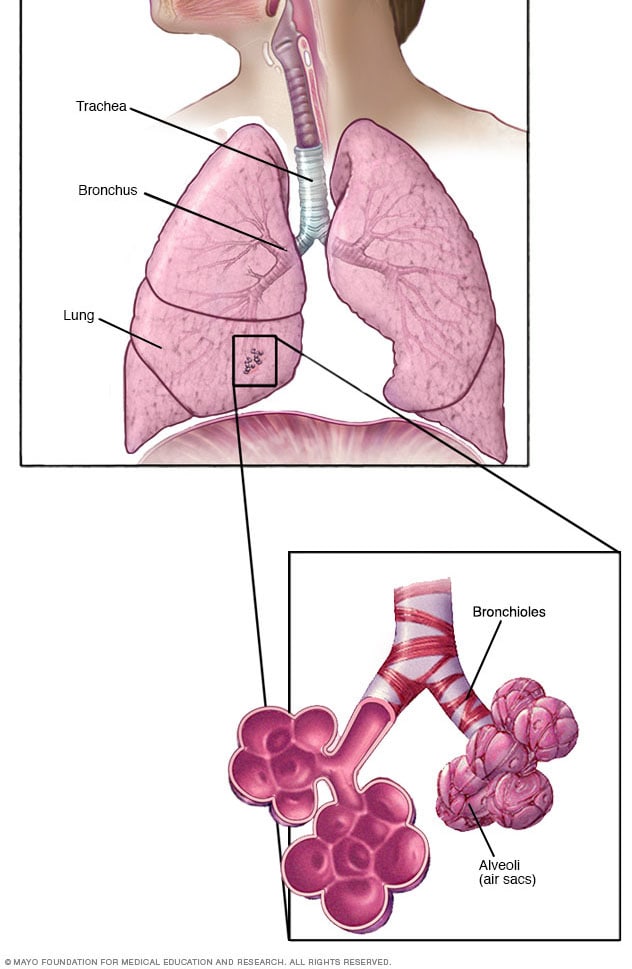

Interstitial Lung Disease - Symptoms And Causes - Mayo Clinic

www.mayoclinic.org

www.mayoclinic.org

bronchioles alveoli lungs lung disease interstitial bronchiolitis cancer bronchi smallest airways air sacs mayo symptoms anatomy main branch into which

IJMS | Free Full-Text | Alveolar-Capillary Membrane-Related Pulmonary